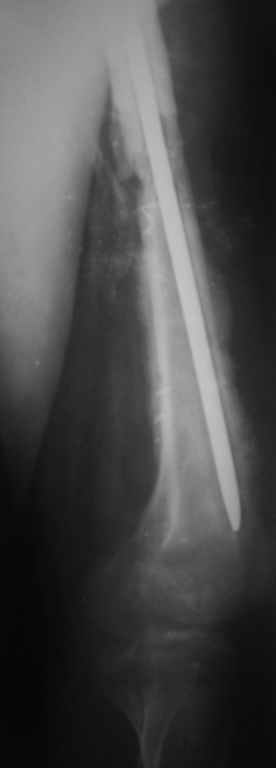

Замена реконструктивного штифта “Custom made Nail” с антибиотиком (рис №5, №6),

после промывки канала с рассверливанием внутреннего кортекса, через 4 недели антибиотический штифт удалили, оспалителный процесс остановлен и бедро сросся.